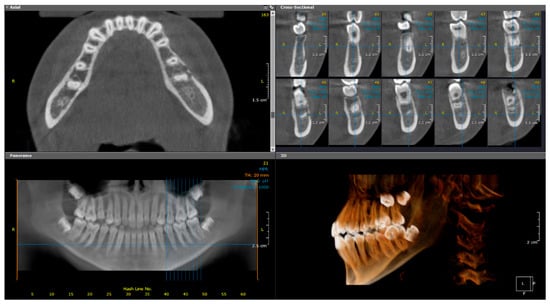

2.4. Case 4

2.4.1. History and Clinical Examination

2.4.2. Radiographic Examination

| 4 | 12 | Left mandible (#37–#43, crossing midline) | Irregular mixed sclerotic/lytic lesion, periosteal reaction, buccolingual expansion | Viable bone with no bacterial colonies | Empirical antibiotics, paracetamol, NSAIDs | CNO confirmed based on recurrence, imaging, and histology | NSAIDs only; no additional therapy needed | Gradual clinical improvement; no recurrence noted |